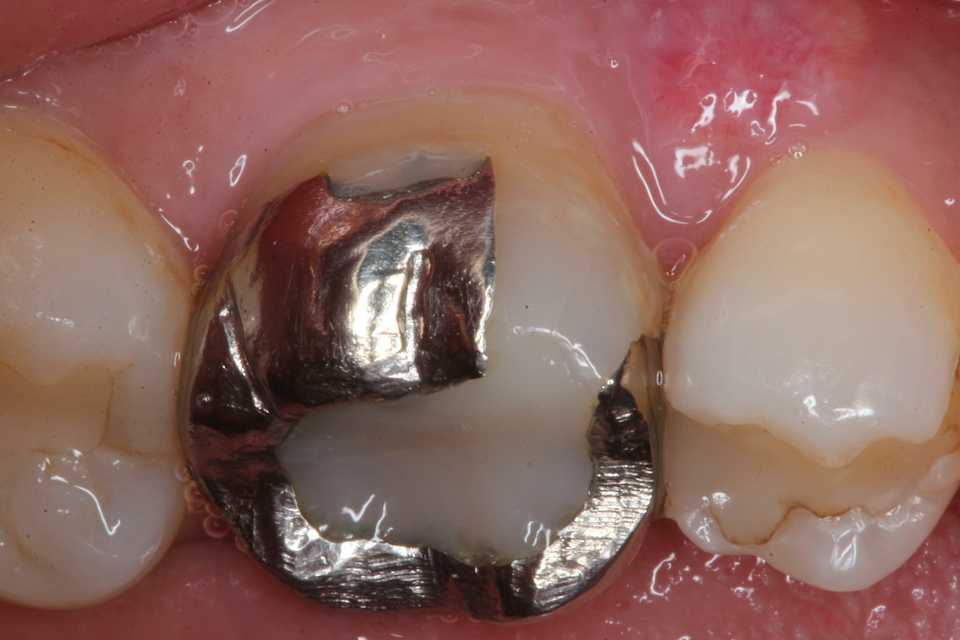

50代女性、左上7、外傷性近心辺縁隆線破折、クラック、自覚症状なし食いしばりの癖がある方で、手前側の6番も補強冠を入れて歯牙破折をなんとか抑えている。この7番も割れて抜歯になる前に補強冠を装着するしかないだろう。とりあえず今日は既存のアマルガムを除去しCRで修復するまで。では時系列でどうぞアマルガムにもクラック(ヒビ)が入っている。クラックα-TCP手前は補強冠、後ろの7番も同じようにするしかないだろう。クラックが深部に進んで離断してしまったら抜歯になる。つづく